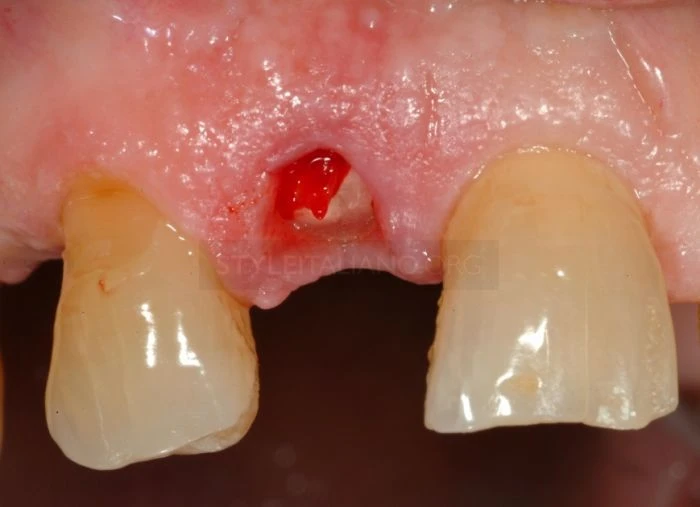

Sau khi tiến hành chuẩn đoán và tiến hành gây tê tại chỗ, các bác sĩ tiến hành nhổ mảnh răng bị gãy.

Vì những khó khăn do vết gãy gây ra các bác sĩ quyết định tạo một đường rạch trong rãnh lợi bằng dao phẫu thuật 5c

Cắt nhú lợi ngoài về phía cuống răng để bảo tồn đám rối mạch máu vùng lợi kẽ răng.

Sau khi lật vạt, thực hiện phẫu thuật tạo hình xương phía ngoài nhưng phải để chân răng có chiều cao tối thiểu 2mm so với mào xương ổ răng. 2mm này rất quan trọng để tạo khoảng trống đủ cho bám dính sinh học.